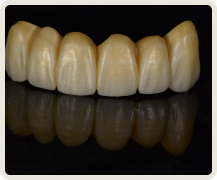

치아 제작시 국내 최고 수준의 장비를 보유한

디지털 치과 전문 기공소와 협업합니다.

Zirconia Crown Design and Milling, Sintering

모든 과정은 이로운치과의 의료진과 디지털 치과기공 전문인 와이앤씨 기공소 와의 긴밀한 커뮤니케이션 하에 협업하여 진행합니다.